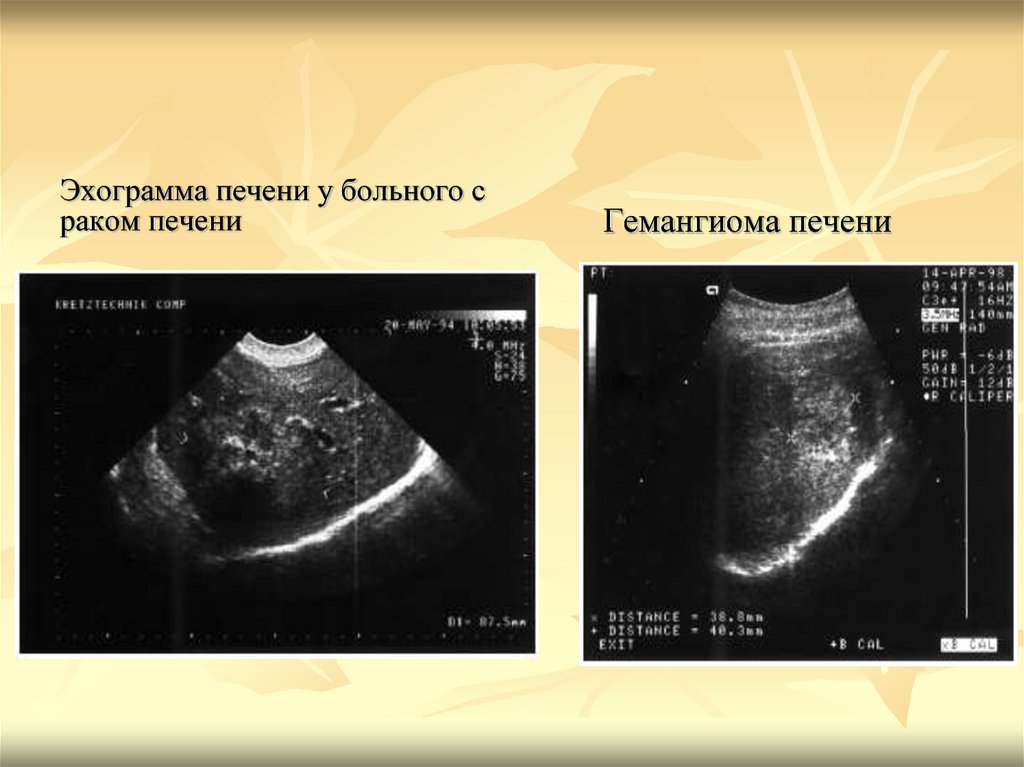

Метастатические поражения печени в ультразвуковом изображении характеризуются